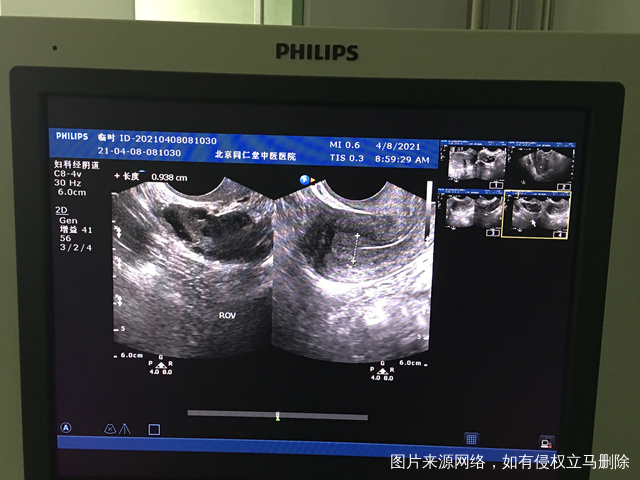

您好我月经不规律上次月经3月2日请问我现在这